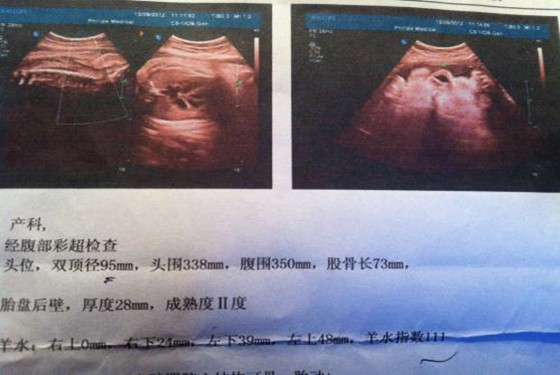

事实上,通过四维彩超是可以很直观立体的查看胎儿器官的,与普通B超相比四维彩超有更高的分辨率,对于胎儿的外生殖器官的辨认会更准确无误,很容易从彩超图中看出区别的。只不过,医院有规定医生即便是知道,也不会直接泄露胎儿的性别。熟一点的医生也只是间接性的提示一下,并不敢直接的告诉你怀的是男孩还是女孩的。这里想要强调的是为了避免误差,建议在怀孕24-28周时做胎儿肢体及脏器方面的检查,虽然怀孕16周时也可以看出胎儿性别,但是它并不是最佳的时机。

@YUHI221:四维彩超肯定能清楚的看出孩子的生殖器,只是医生不说罢了。我一个做医生的朋友透露过,女孩的生殖器图片为三条线,而男孩的生殖器图片好像蘑菇一样是凸起来的。

@sawqe:老家有熟人去医院做彩超时人家就提示过怀的是女孩,说是小棉袄之类的提示语,果然生下来是女孩,而且彩超图片上看到生殖器处有三条线的图样。